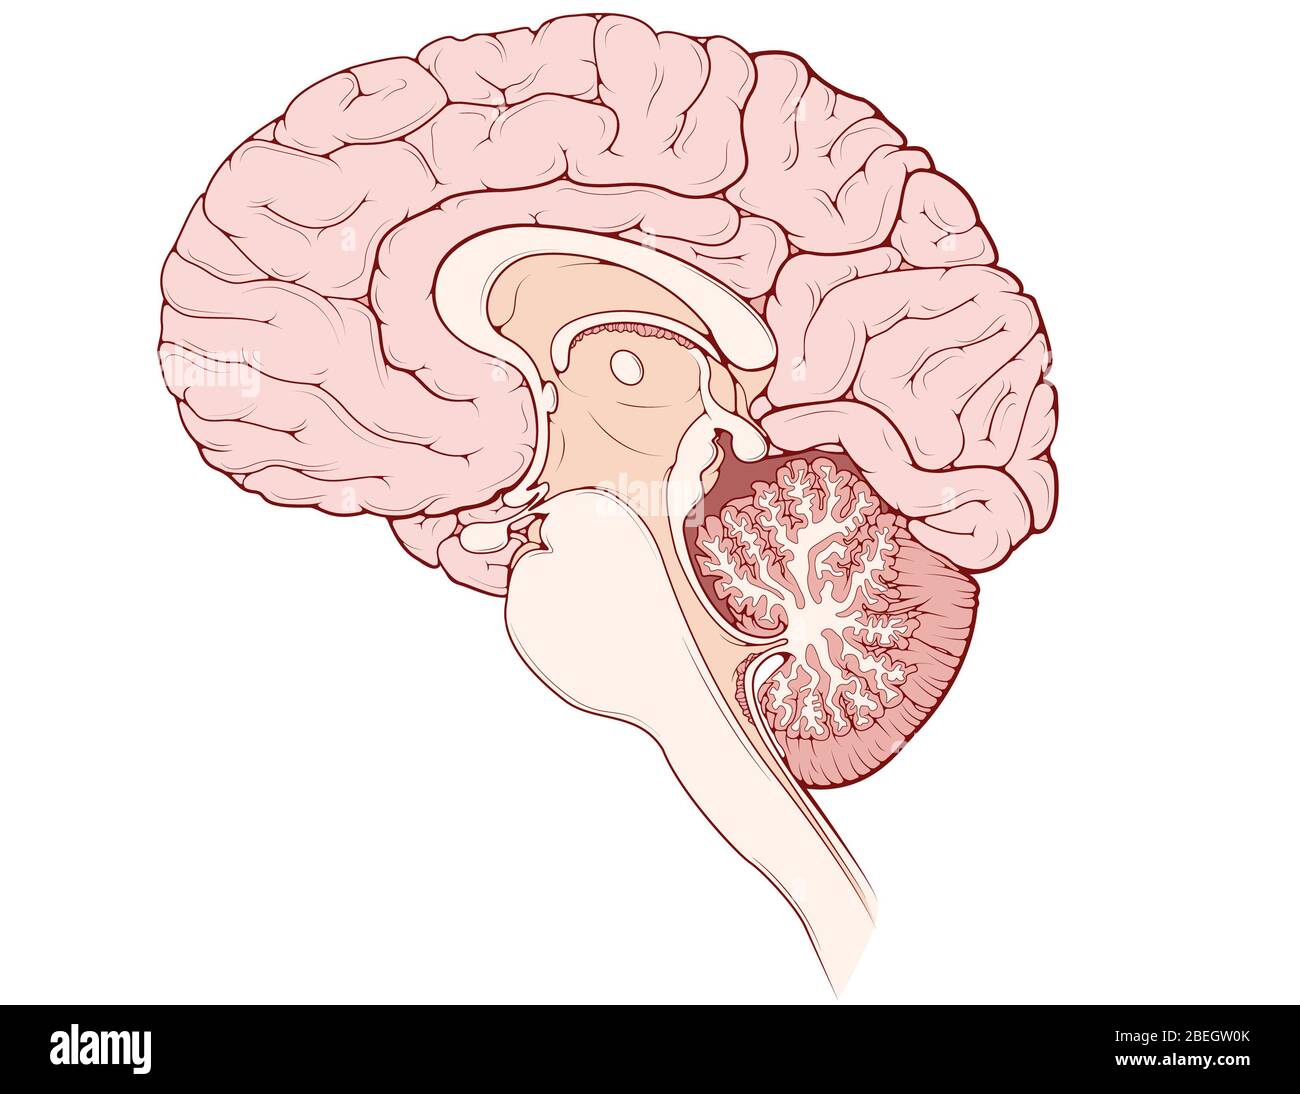

RMBCE641–Sagittale Abschnitt des menschlichen Gehirns, Darstellung von Strukturen der zerebralen Ventrikel, Kleinhirn und Hirnstamm.

RM2AWFNN9–Menschliche Anatomie, einschließlich Struktur und Entwicklung und praktische Überlegungen d in einem sagittalen mesialen Abschnitt (Abb. 910) wird jede dieser Teilungen als mit einem Teil des Systems der Kommunikation von Räumen verwandt angesehen, die als die dritten Ventrikel des Lateralands, der Aquädukt von Sylvius und der vierte Ventrikel die oben genannten Gehirnhemisphären ausdehnen. Durch den Hirnstamm und unter dem Kleinhirn bis zum zentralen Kanal des Rückenmarks. Da die lateralen Ventrikel zwei innumerieren, ist die Theirstellung im Zusammenhang mit den Gehirnhemisphären, in denen sie liegen, lateral zum m